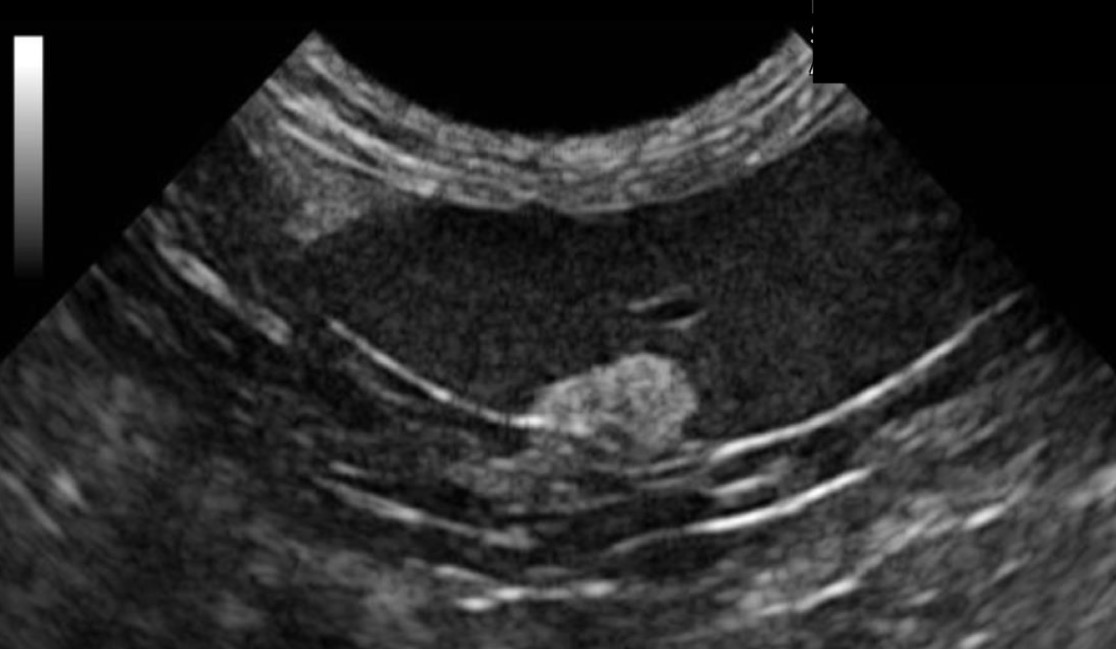

Hyperechoic splenic mass

What anomaly is being observed in this ultrasound?

Splenic hemangiosarcome

What organ is being affected and by what?